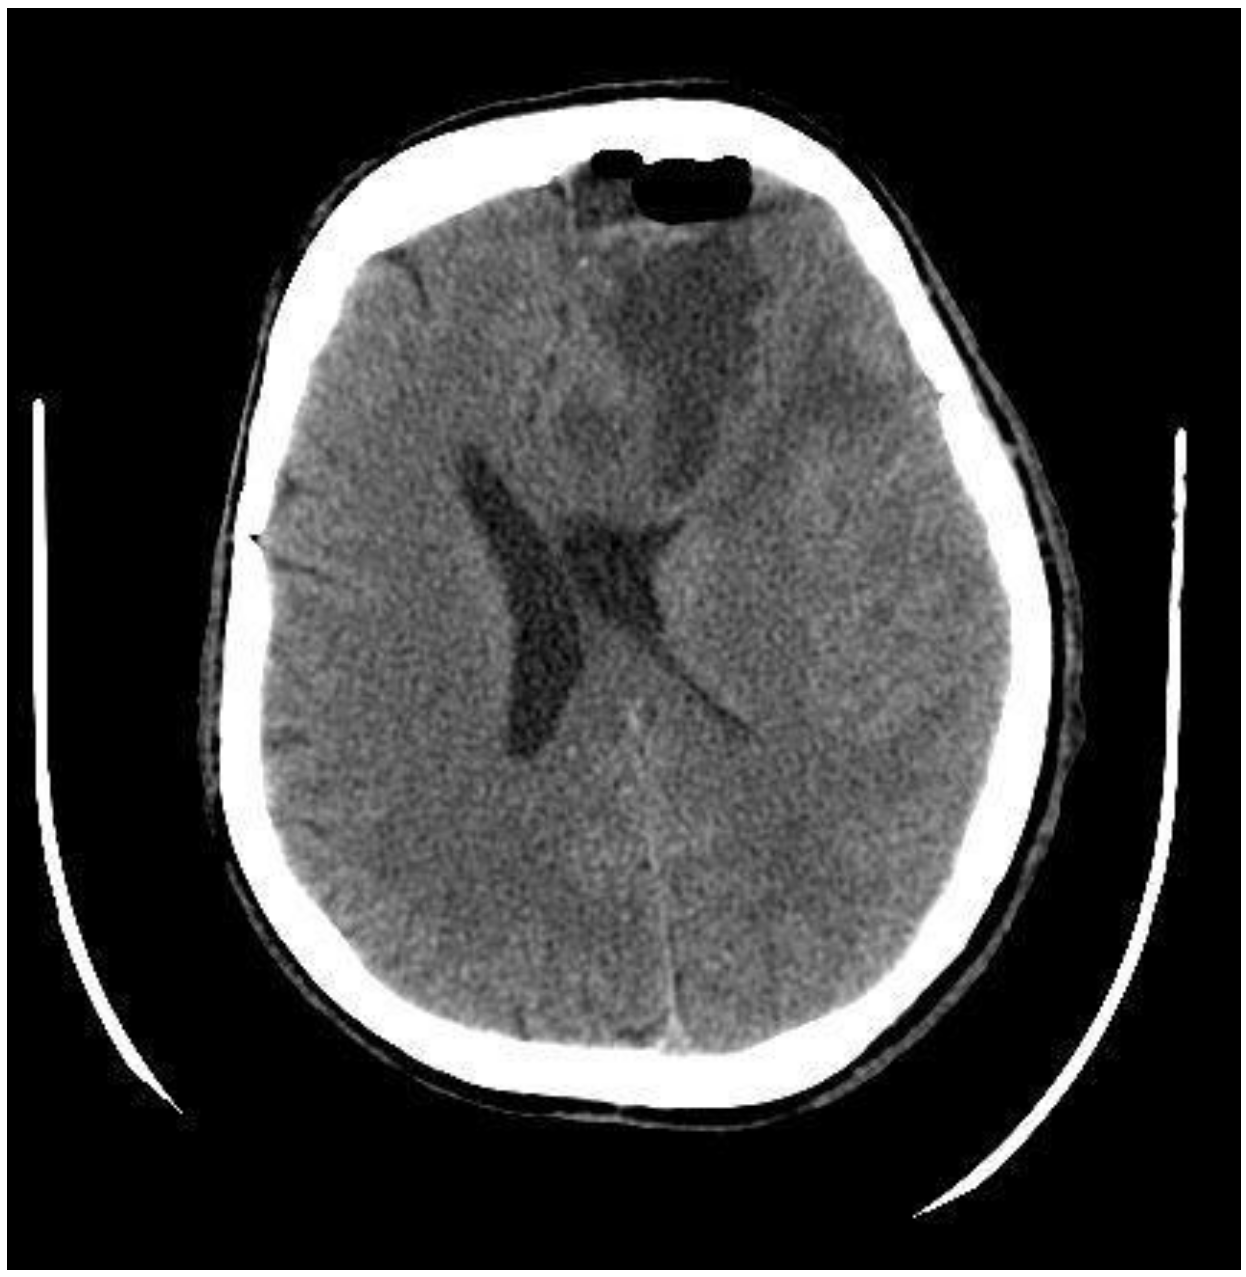

2. Case Presentation